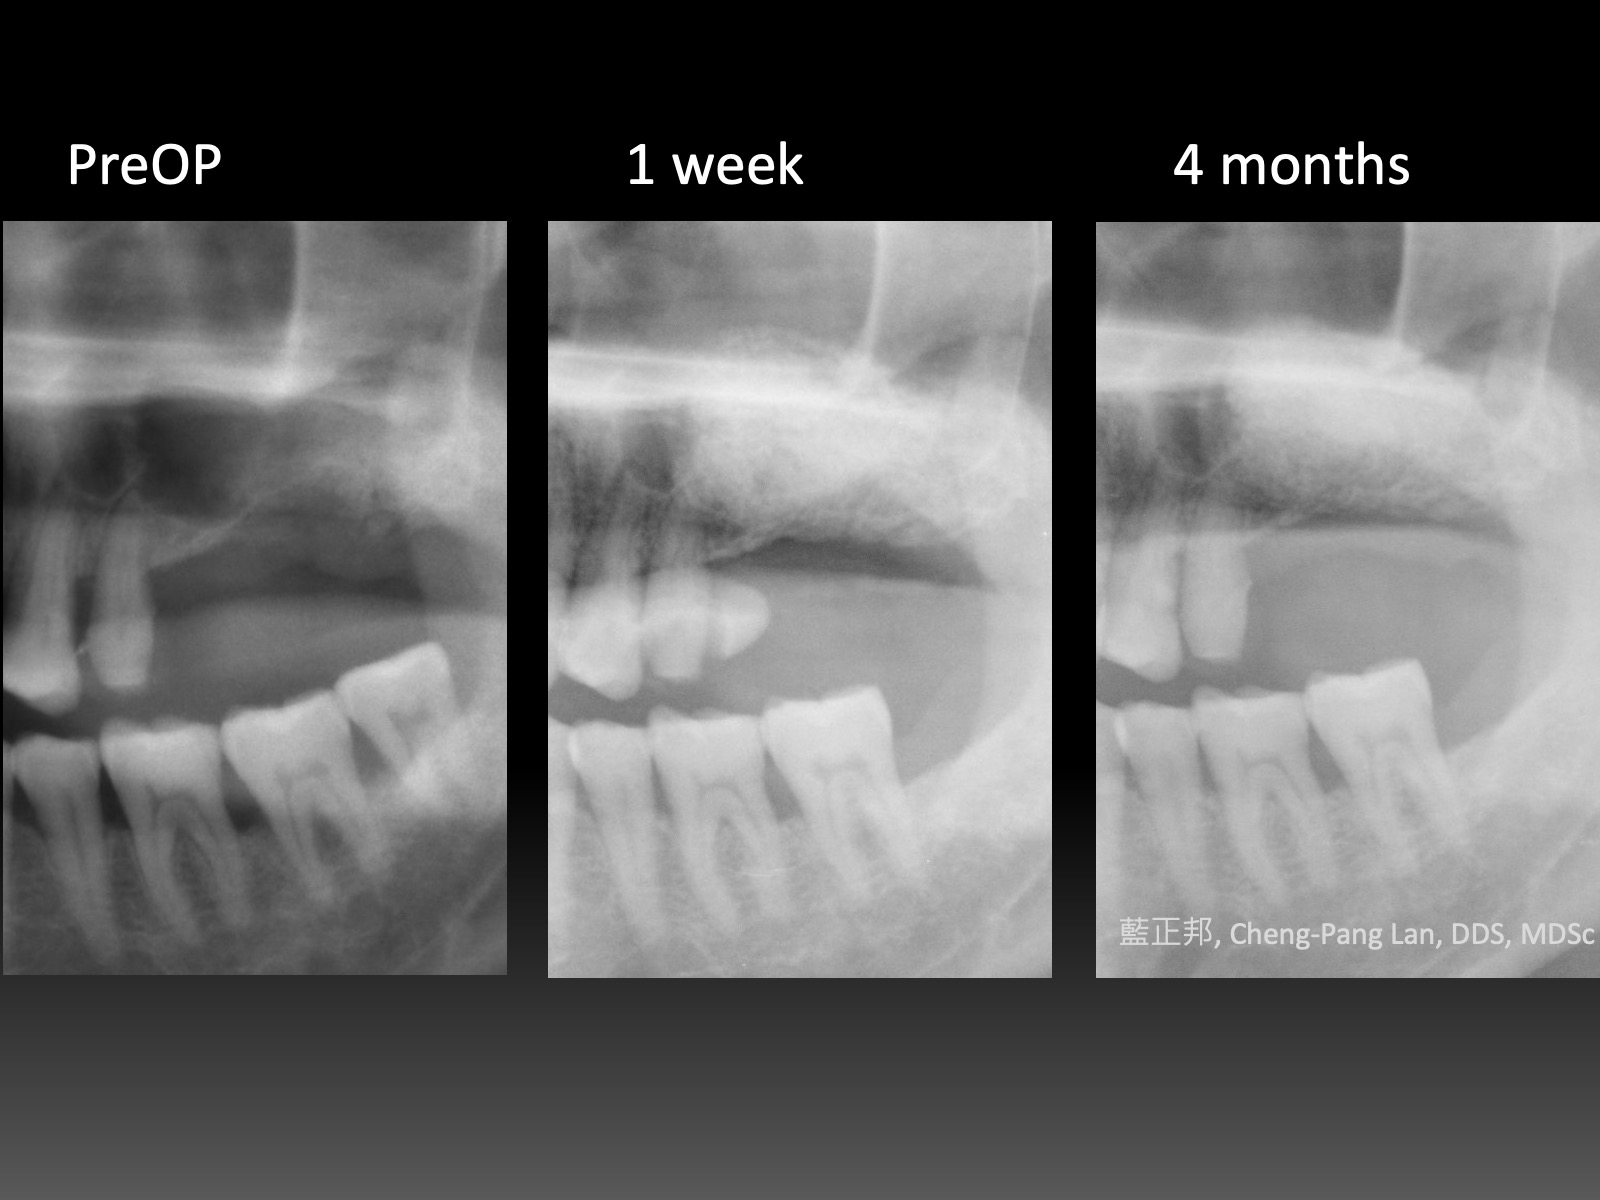

12 Years of Lateral-window Sinus Lift

2010年,台大第二年剛開始。這是我第一台鼻竇開窗手術,還記得很快地用骨刀切割,順利進入鼻竇。

但是翻到後面,遇到困難,只翻一半就遇到瓶頸,由台大老師接手翻完,之後回到我再放入材料並縫合。

這十二年來,口內狀態,加上X光檢查,一直都算穩定。但是回顧起來,病患其實血糖不低,加上抽菸,危險因子算多了。

如果其他的病患,危險因子一旦多,牙周穩定性會明顯變差,至少這個病患到現在為止還沒有。

到底是運氣好呢?還是有其他未知因素影響?又或許位於常態分佈—鐘型曲線兩端的極少數族群?

我也不知道。至少第一台十二年來慶祝一下~~

回顧還發現,其實第一次做開窗就用手繪圖了,有興趣如何準備開窗手術的初學者,我寫了一篇在這裡